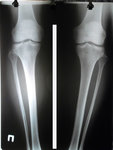

Дата операции 21.08.2015г.

Дата снятия аппаратов 16.12.2015г.

Срок лечения 114 дней.

SAM_0007.JPG

SAM_0009.JPG

В АППАРАТАХ ПЕРЕД СНЯТИЕМ